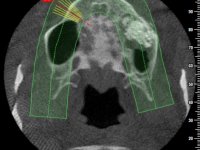

The patient was proposed to undergo a fixed oral rehabilitation consisting of a 2-element bridge over teeth 11 and 21 and a 5-element bridge over 3 implants that would be placed in the location of teeth 22, 24 and 26. The prosthetic structures would have an infrastructure in Zr coated with ceramic and the bridge over the implants would be screwed. The indicated extraction of teeth 25 and 26 and placement of an implant in the 26 site would imply surgery to fill the maxillary sinus. As the patient showed interest in having fixed temporary rehabilitation during treatment, we divided the treatment into 6 phases to achieve this goal: 1- Placement of a temporary bridge over teeth 11,21,25 and 26. With tooth extraction 24. 2- Placement of 2 implants in the location of teeth 22 and 24. 3- Placement of a temporary 6-element bridge over teeth 11 and 21 and over the implants. 4- Carrying out surgery to fill the maxillary sinus. 5 – Placement of the implant in the location of tooth 26 and in the area where the filling of the maxillary sinus was made. 6 – Placement of the definitive work.

A temporary acrylic bridge made in the laboratory with 7 elements was made, with teeth 11,21, 25 and 26 as pillars. The old bridge was removed and tooth 24 was extracted. The provisional bridge after relining was cemented in the mouth. Two implants were placed in the teeth 22 and 24 and 3 months after this intervention an impression was made to make a temporary bridge screwed over the implants and cemented to the teeth. The bridge was placed in the mouth and teeth 25 and 26 were extracted. 3 months later, surgery was performed to fill the maxillary sinus and 6 months later the implant was placed in the location of tooth 26. After osseointegration of this implant, the final impression was made for the final work. The bridge over the implants was permanently screwed on and the bridge over the teeth was cemented with resin-reinforced glass ionomer cement.

Maxillary sinus filling surgery was performed by colleague Dr. Ivo Teixeira Lopes